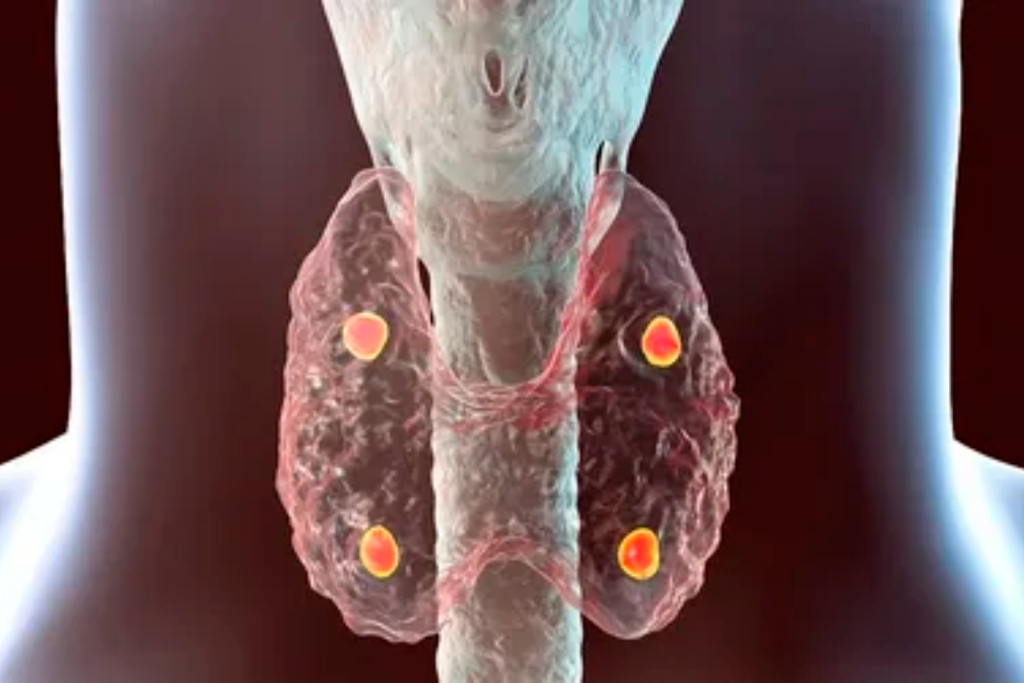

Goiter

Thyroid nodules

Hypothyroidism

Hashimoto Thyroiditis

Hyperthyroidism

Grave’s disease

Hypercalcemia

Hyperparathyroidism